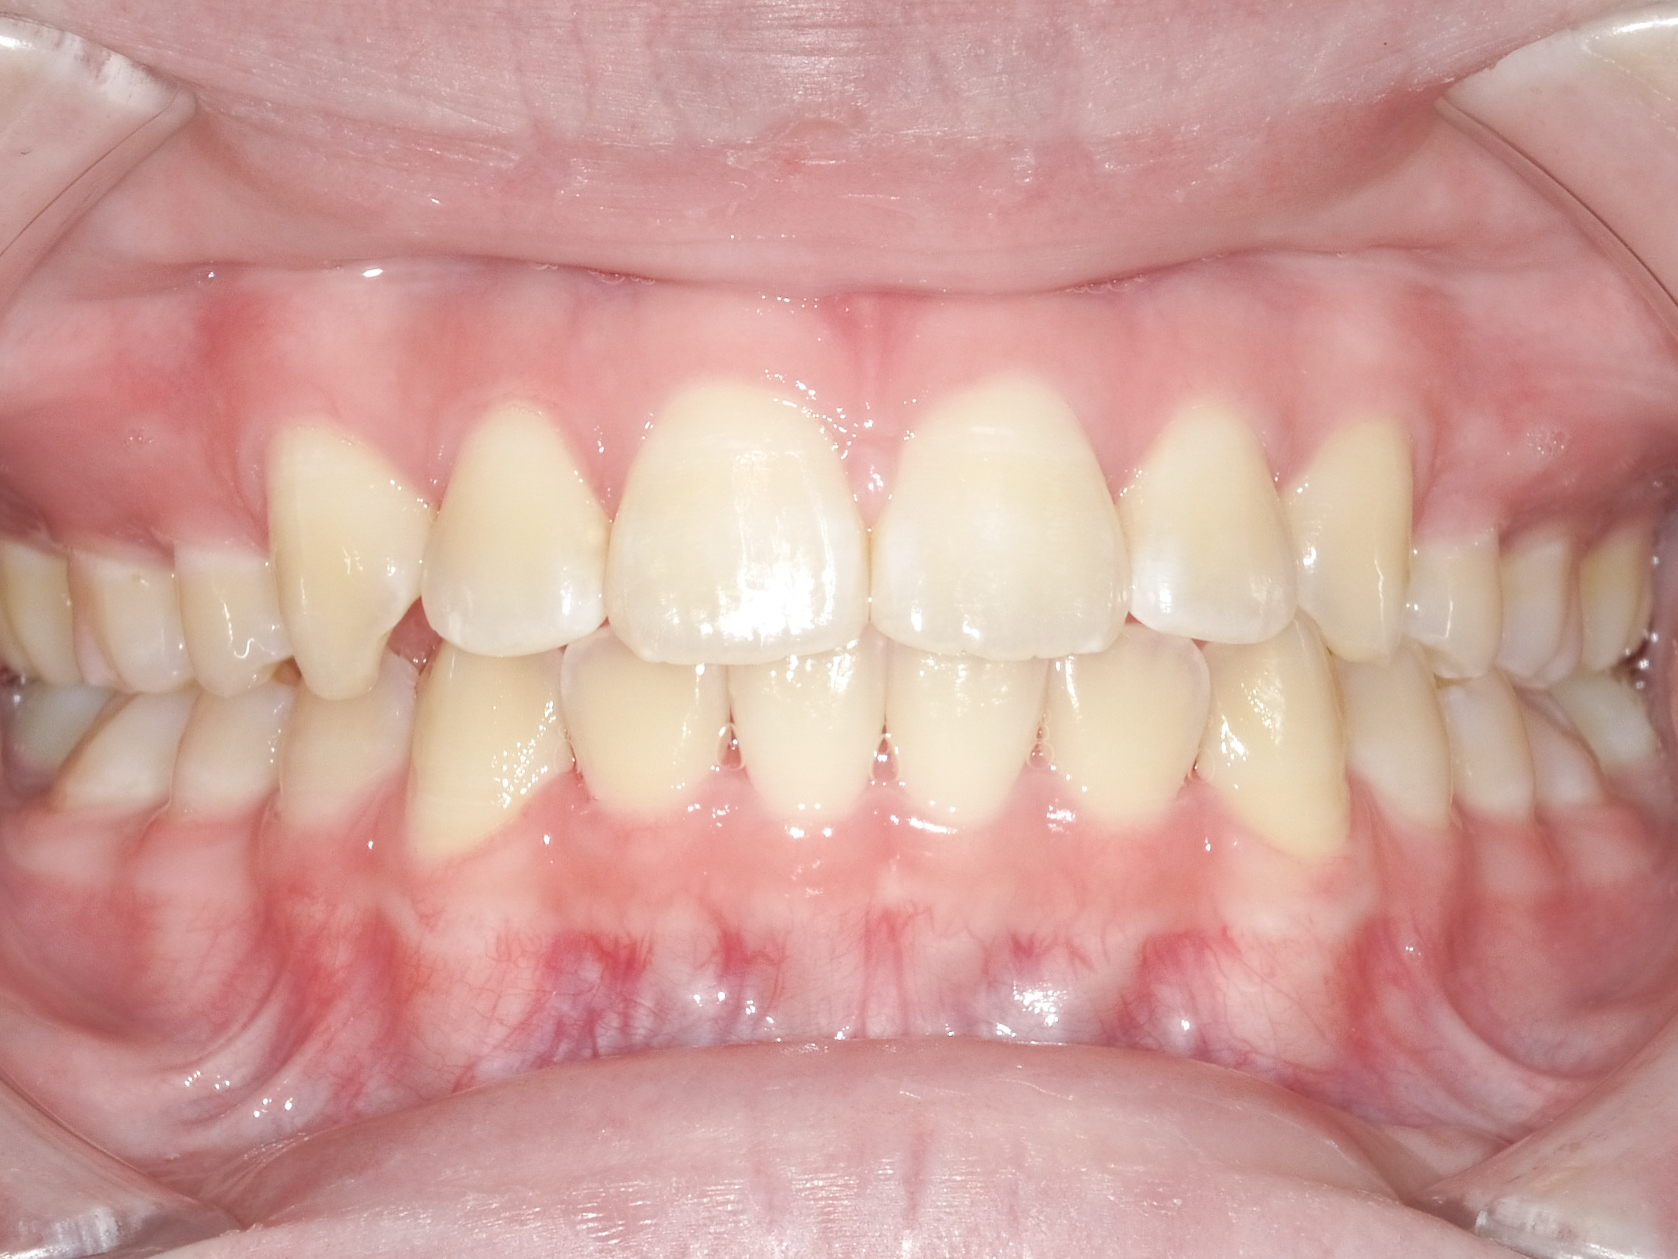

After

正面から見てもきれいに並んでおり、上下の真ん中の線も一致しました。